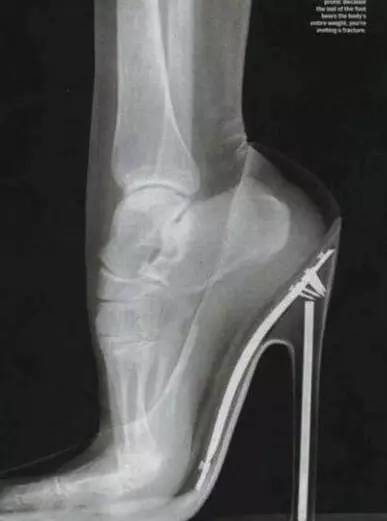

透过X光可以看见被挤压变形的脚骨

让女人“又爱又恨”的——高跟鞋!